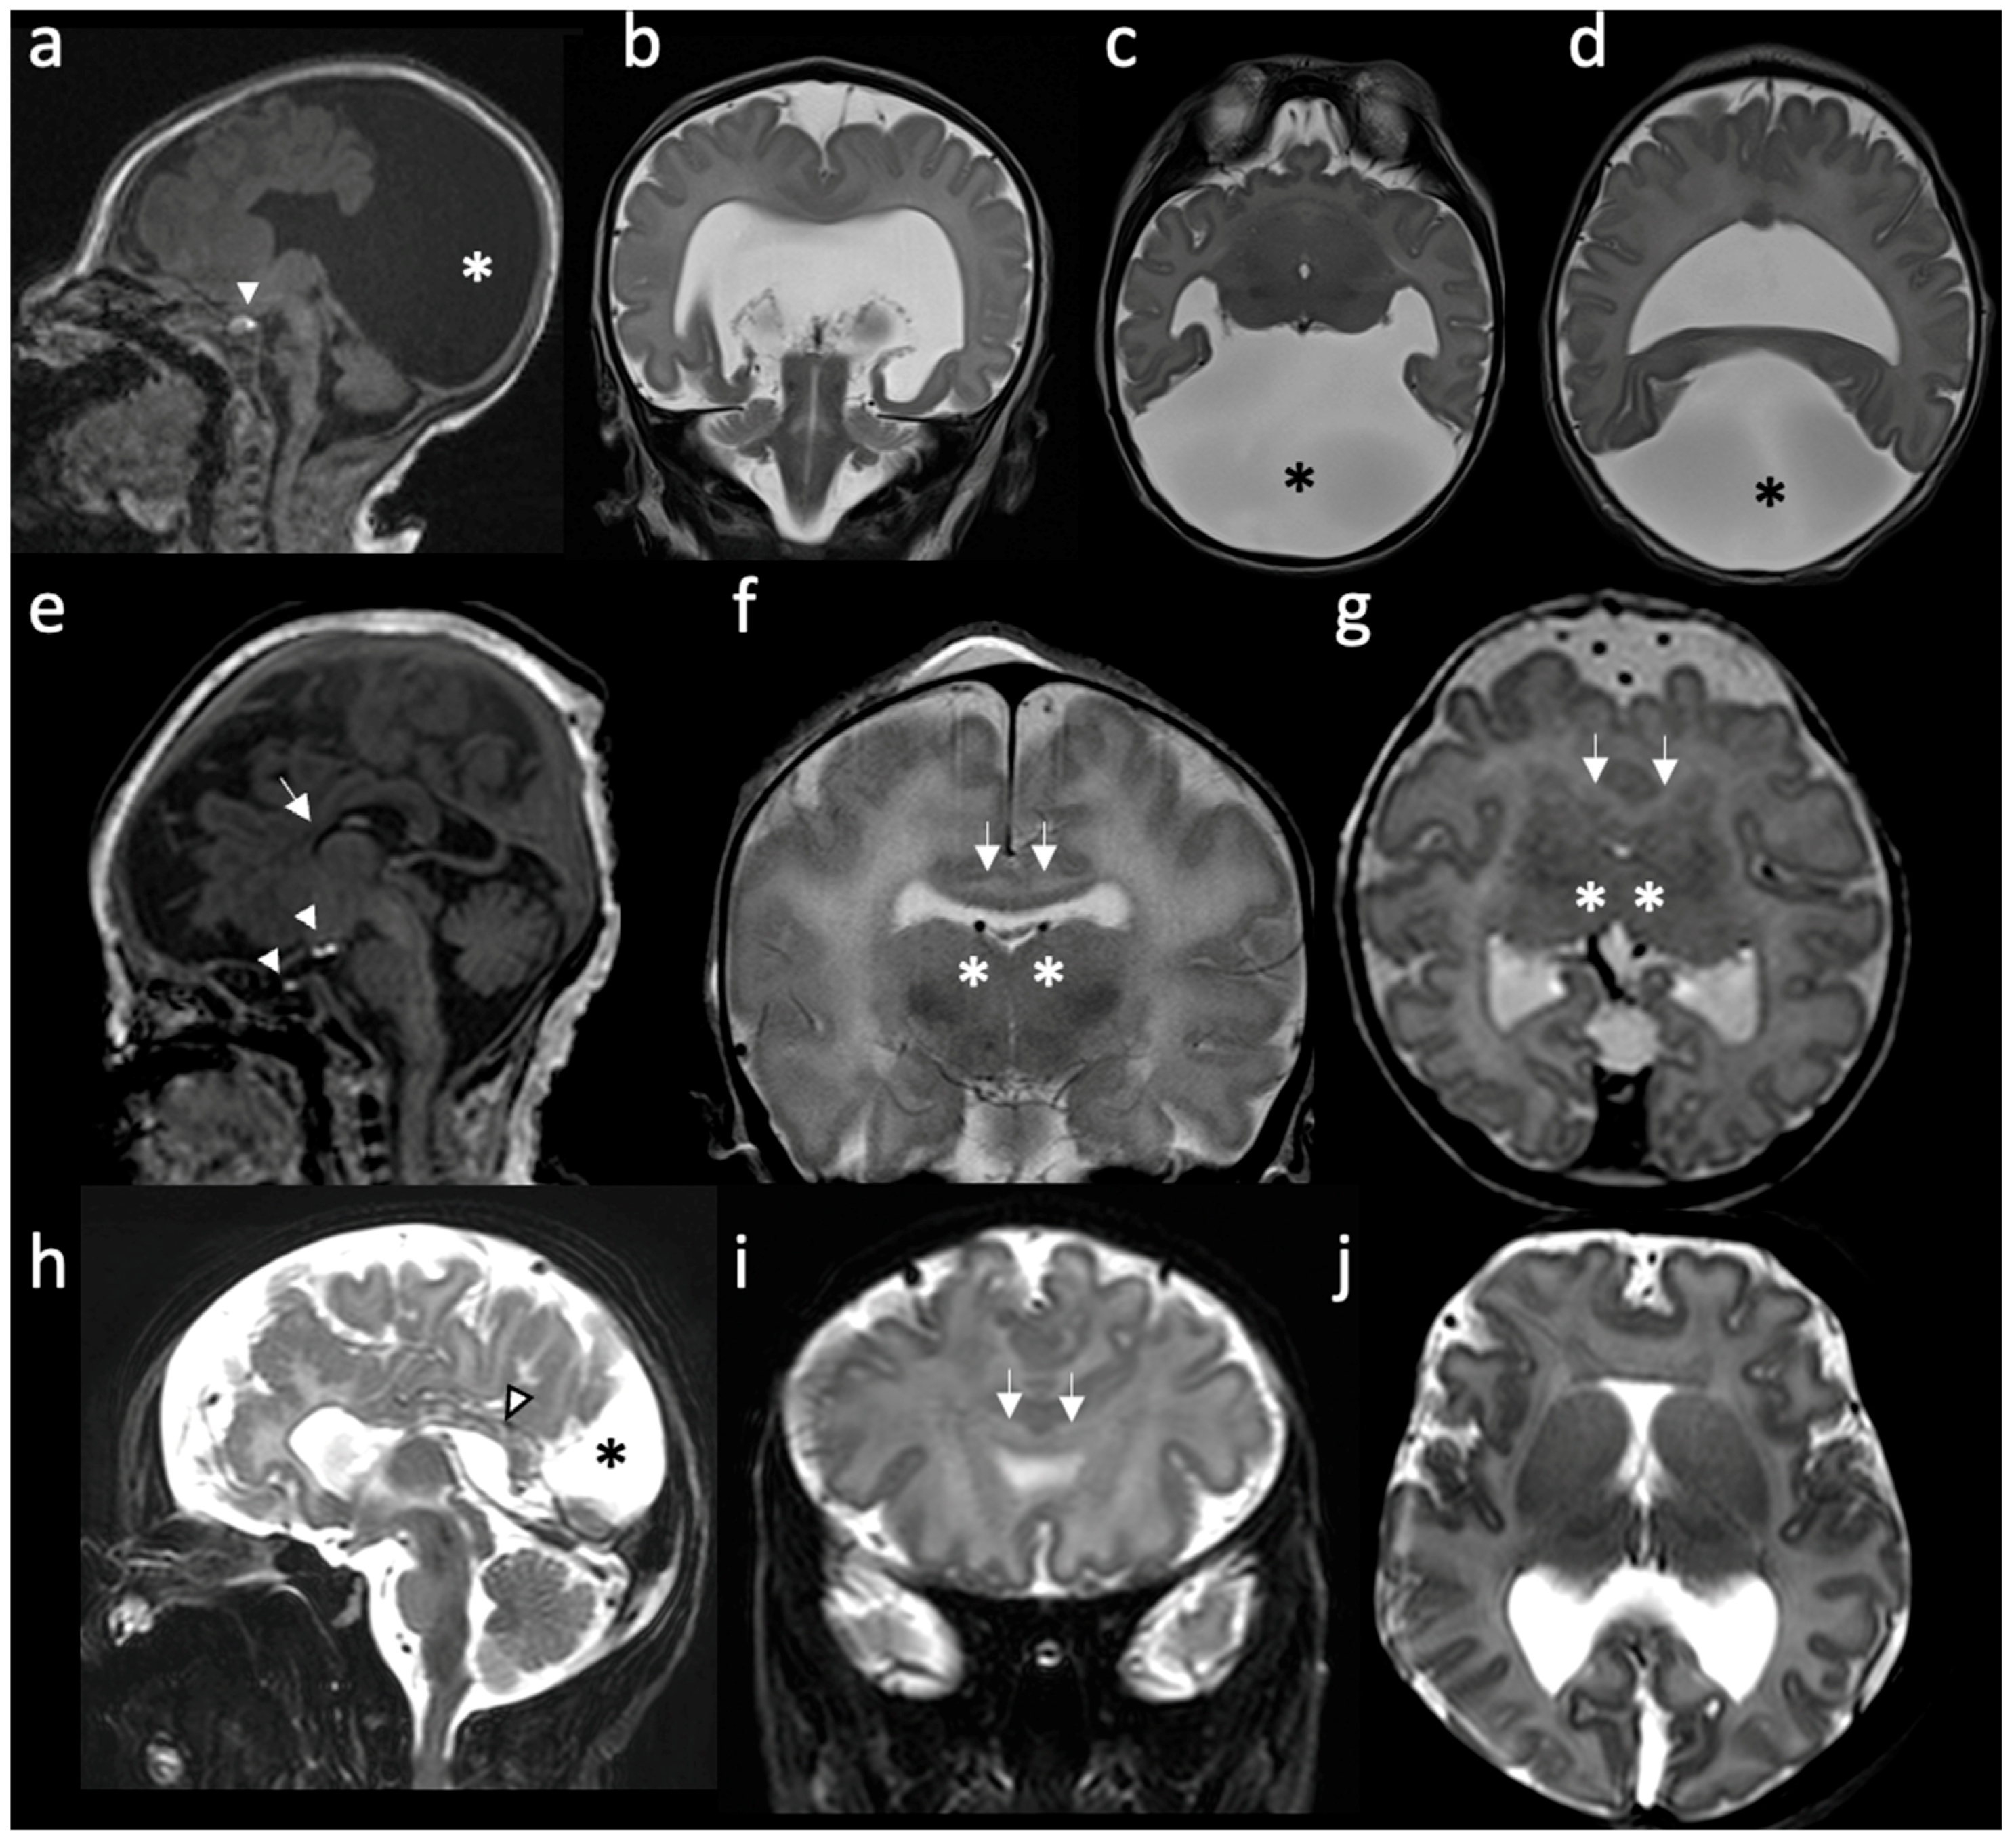

Figure 1. Radiologic features of holoprosencephalies: (ad) Radiologic features of alobar holoprosencephaly, 2 days old. (a) Sagittal T1-weighted image shows hypodevelopment of the parietal lobes with absence of identifiable occipital lobes and corpus callosum. The bright T1 spot of the neurohypophysis is preserved and well placed (white arrowhead). (b) Coronal T2-weighted image shows the frontal lobes fused across the midline and a large supratentorial monoventricle. (c,d) Axial T2-weighted images show fused thalami and the monoventricle communicating with a large dorsal cyst (asterisk), noting the absence of the septum pellucidum and rudimentary formation of the temporal horns. (eg) Radiologic features of semilobar holoprosencephaly, 3 days old. (e) Sagittal T1-weighted image shows hypoplastic frontal lobes, absence of anterior corpus callosum (white arrow) and abnormal finding of partial ectopic neural hypophysis associated with residual hyperintense signal seen within the sella (white arrowheads). (f) Coronal T2-weighted image shows fusion of the frontal lobes (white arrows) and partial fusion of thalami (asterisk). (g) Axial T2-weighted image shows that the division of the ventricles is only seen posteriorly. Septum pellucidum is absent. (hj) Radiologic features of middle interhemispheric variant holoprosencephaly, 15 days old. (h) Sagittal T2-weighted image shows absent body of the corpus callosum but with the presence of the splenium (white arrowhead). Dorsal interhemispheric cyst is present (black asterisk). (i) Coronal T2-weighted image shows fusion of the frontal lobes across the midline (white arrows). Note that the degree of fusion is less extensive than the one seen in the semilobar HPE. (j) Axial T2-weighted image shows fused frontal lobes, absent septum pellucidi and the interhemispheric cyst in the occipital region.

Since then, a few more categories have been added to the original classification. The middle interhemispheric (MIH) variant is characterized by the separation of the anterior and occipital regions of the brain’s hemispheres, while the posterior frontal and parietal lobes remain fused [17] (Figure 1h–j). Milder, minimal and microforms of HPE are also described and are, respectively, associated with septo-optic dysplasia, nonseparation of the preoptic area, and only facial features (hypotelorism and a single maxillary central incisor) with normal brain development [10][15][18]. The radiologic features of holoprosencephalies are summarized in Table 1.